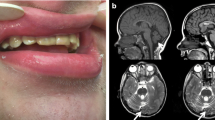

Fourteen individual cases and clinical characteristics were summarized in Tables 5 and 6. The nationality of the cases is not recorded in the publications. Eleven cases were described in the USA (cases 1–11, Table 4). One case was reported in the UK (case 12, Table 4), another in Iran (case 13, Table 4), and the last in India (case 14, Table 4). Severe intellectual disability (ID) or global development delay was present in twelve cases—eleven cases with significant gait disturbance, including 3 cases without gait. Cerebellar atrophy was identified in nine subjects. None of the cases reported seizures, except case 14, with a history of a single episode of myoclonus at 5 years of age. Three cases did not report defects in dental enamel.

The phenotype of most cases includes developmental and language delay, intellectual disability, motor disturbance, muscle weakness, hypotonia, and cerebellar signs such as ataxia and dysarthria mainly, in addition to dental abnormalities and evidence of cerebellar and vermix atrophy. In some cases, cognitive, motor, and language regression were reported. A case of neurodegeneration and death at 16 years old.